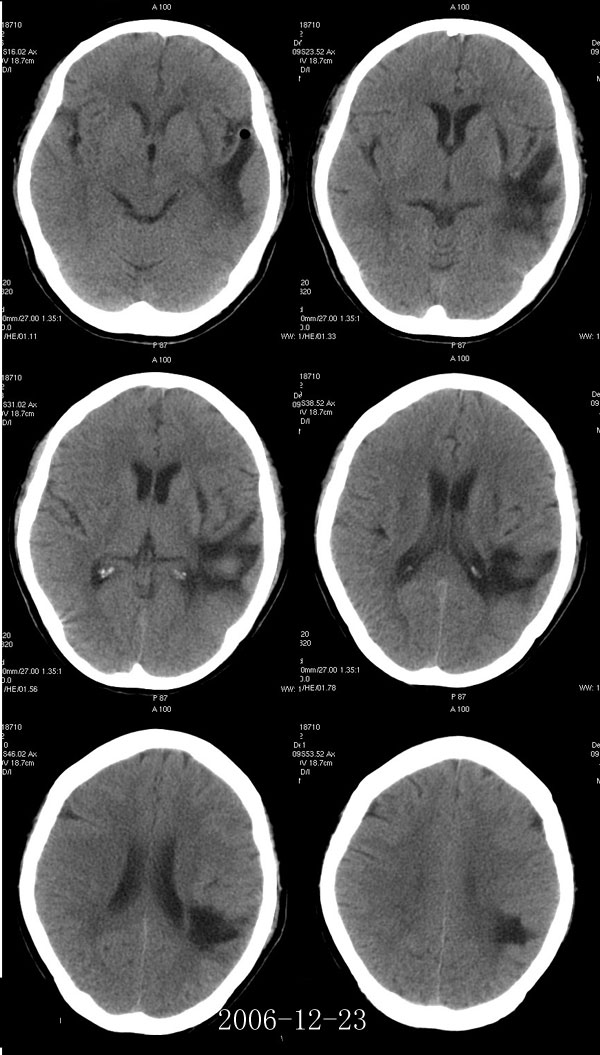

腔隙性脑梗塞能活多久

回答您好 腔隙性脑梗死是一种很小的梗死灶,直径一般不超过15厘米这种梗死多发生在大脑深部的基底节区以及脑干等部位这种情况后遗症比较少,一般不影响生命的,需要及时治疗和注意防止复发;回答您好! 问题分析首先腔隙性脑梗塞...